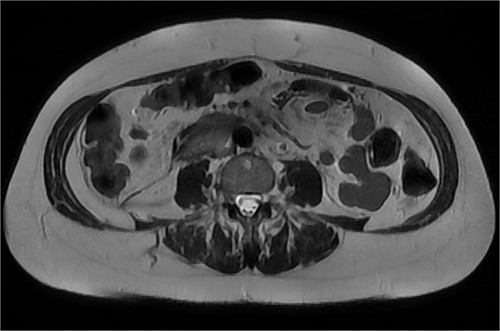

After further discussion with the reporting radiologist, a magnetic resonance imaging (MRI) was performed, which confirmed the presence of an acute periduodenal hematoma surrounding D2 and D3, lying in the retroperitoneal space, anterior to the right perirenal space. Etiology was uncertain. No abnormal enhancement within the bowel to suggest a bowel wall lesion or infiltrating mass (Figs 3 and 4).

MRI abdomen, axial view. T2 hypointense, T1 iso to hyperintense material surrounding D2/D3 without enhancement in keeping with hemorrhage. No vascular or bowel wall lesion identified.